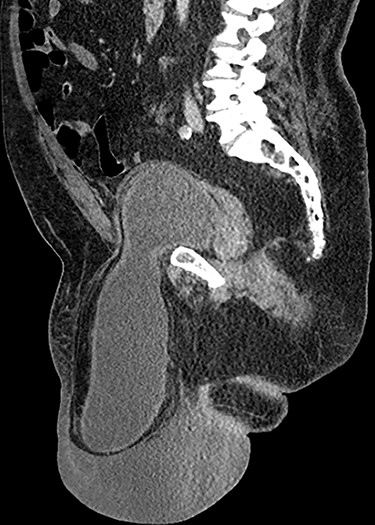

Computed tomography (CT) scan of the abdomen and pelvis with contrast revealed a large right indirect inguinal hernia containing a significant portion of the bladder within the scrotum (Figs 1–3). There was associated bilateral hydronephrosis and hydroureter, and significant scrotal oedema seen within the soft tissues.

Coronal CT image of the abdomen and pelvis demonstrating herniation of the bladder through the inguinal canal into the scrotum, with associated oedema of the scrotal soft tissues.